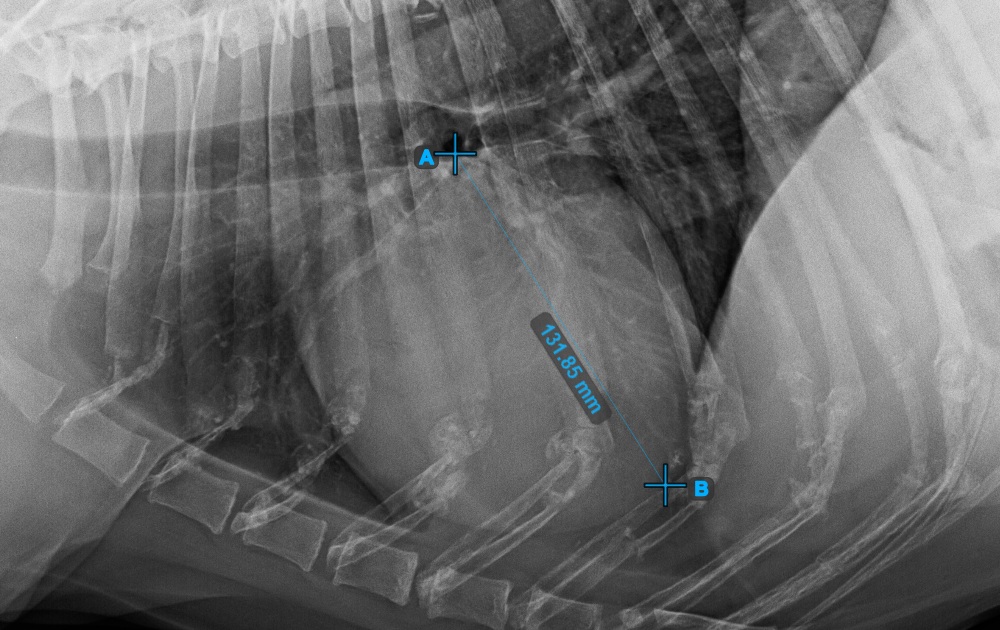

Complete the long axis of the heart by marking the Apex point, near the bottom of the heart.

The image below represents a typical placement of the Apex point.